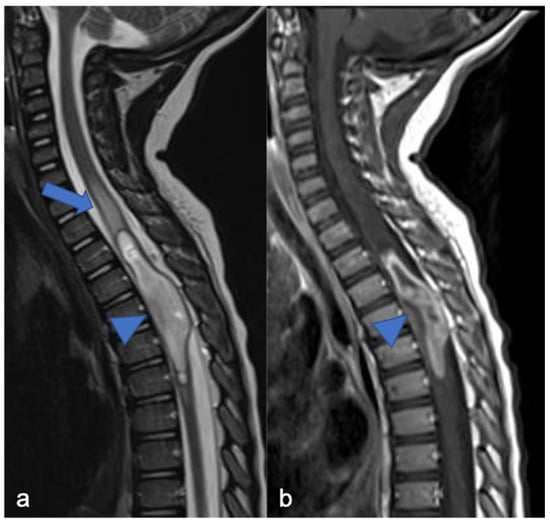

2. Gliomas and Mixed Neuronal–Glial Tumors

2.1. Gliomas